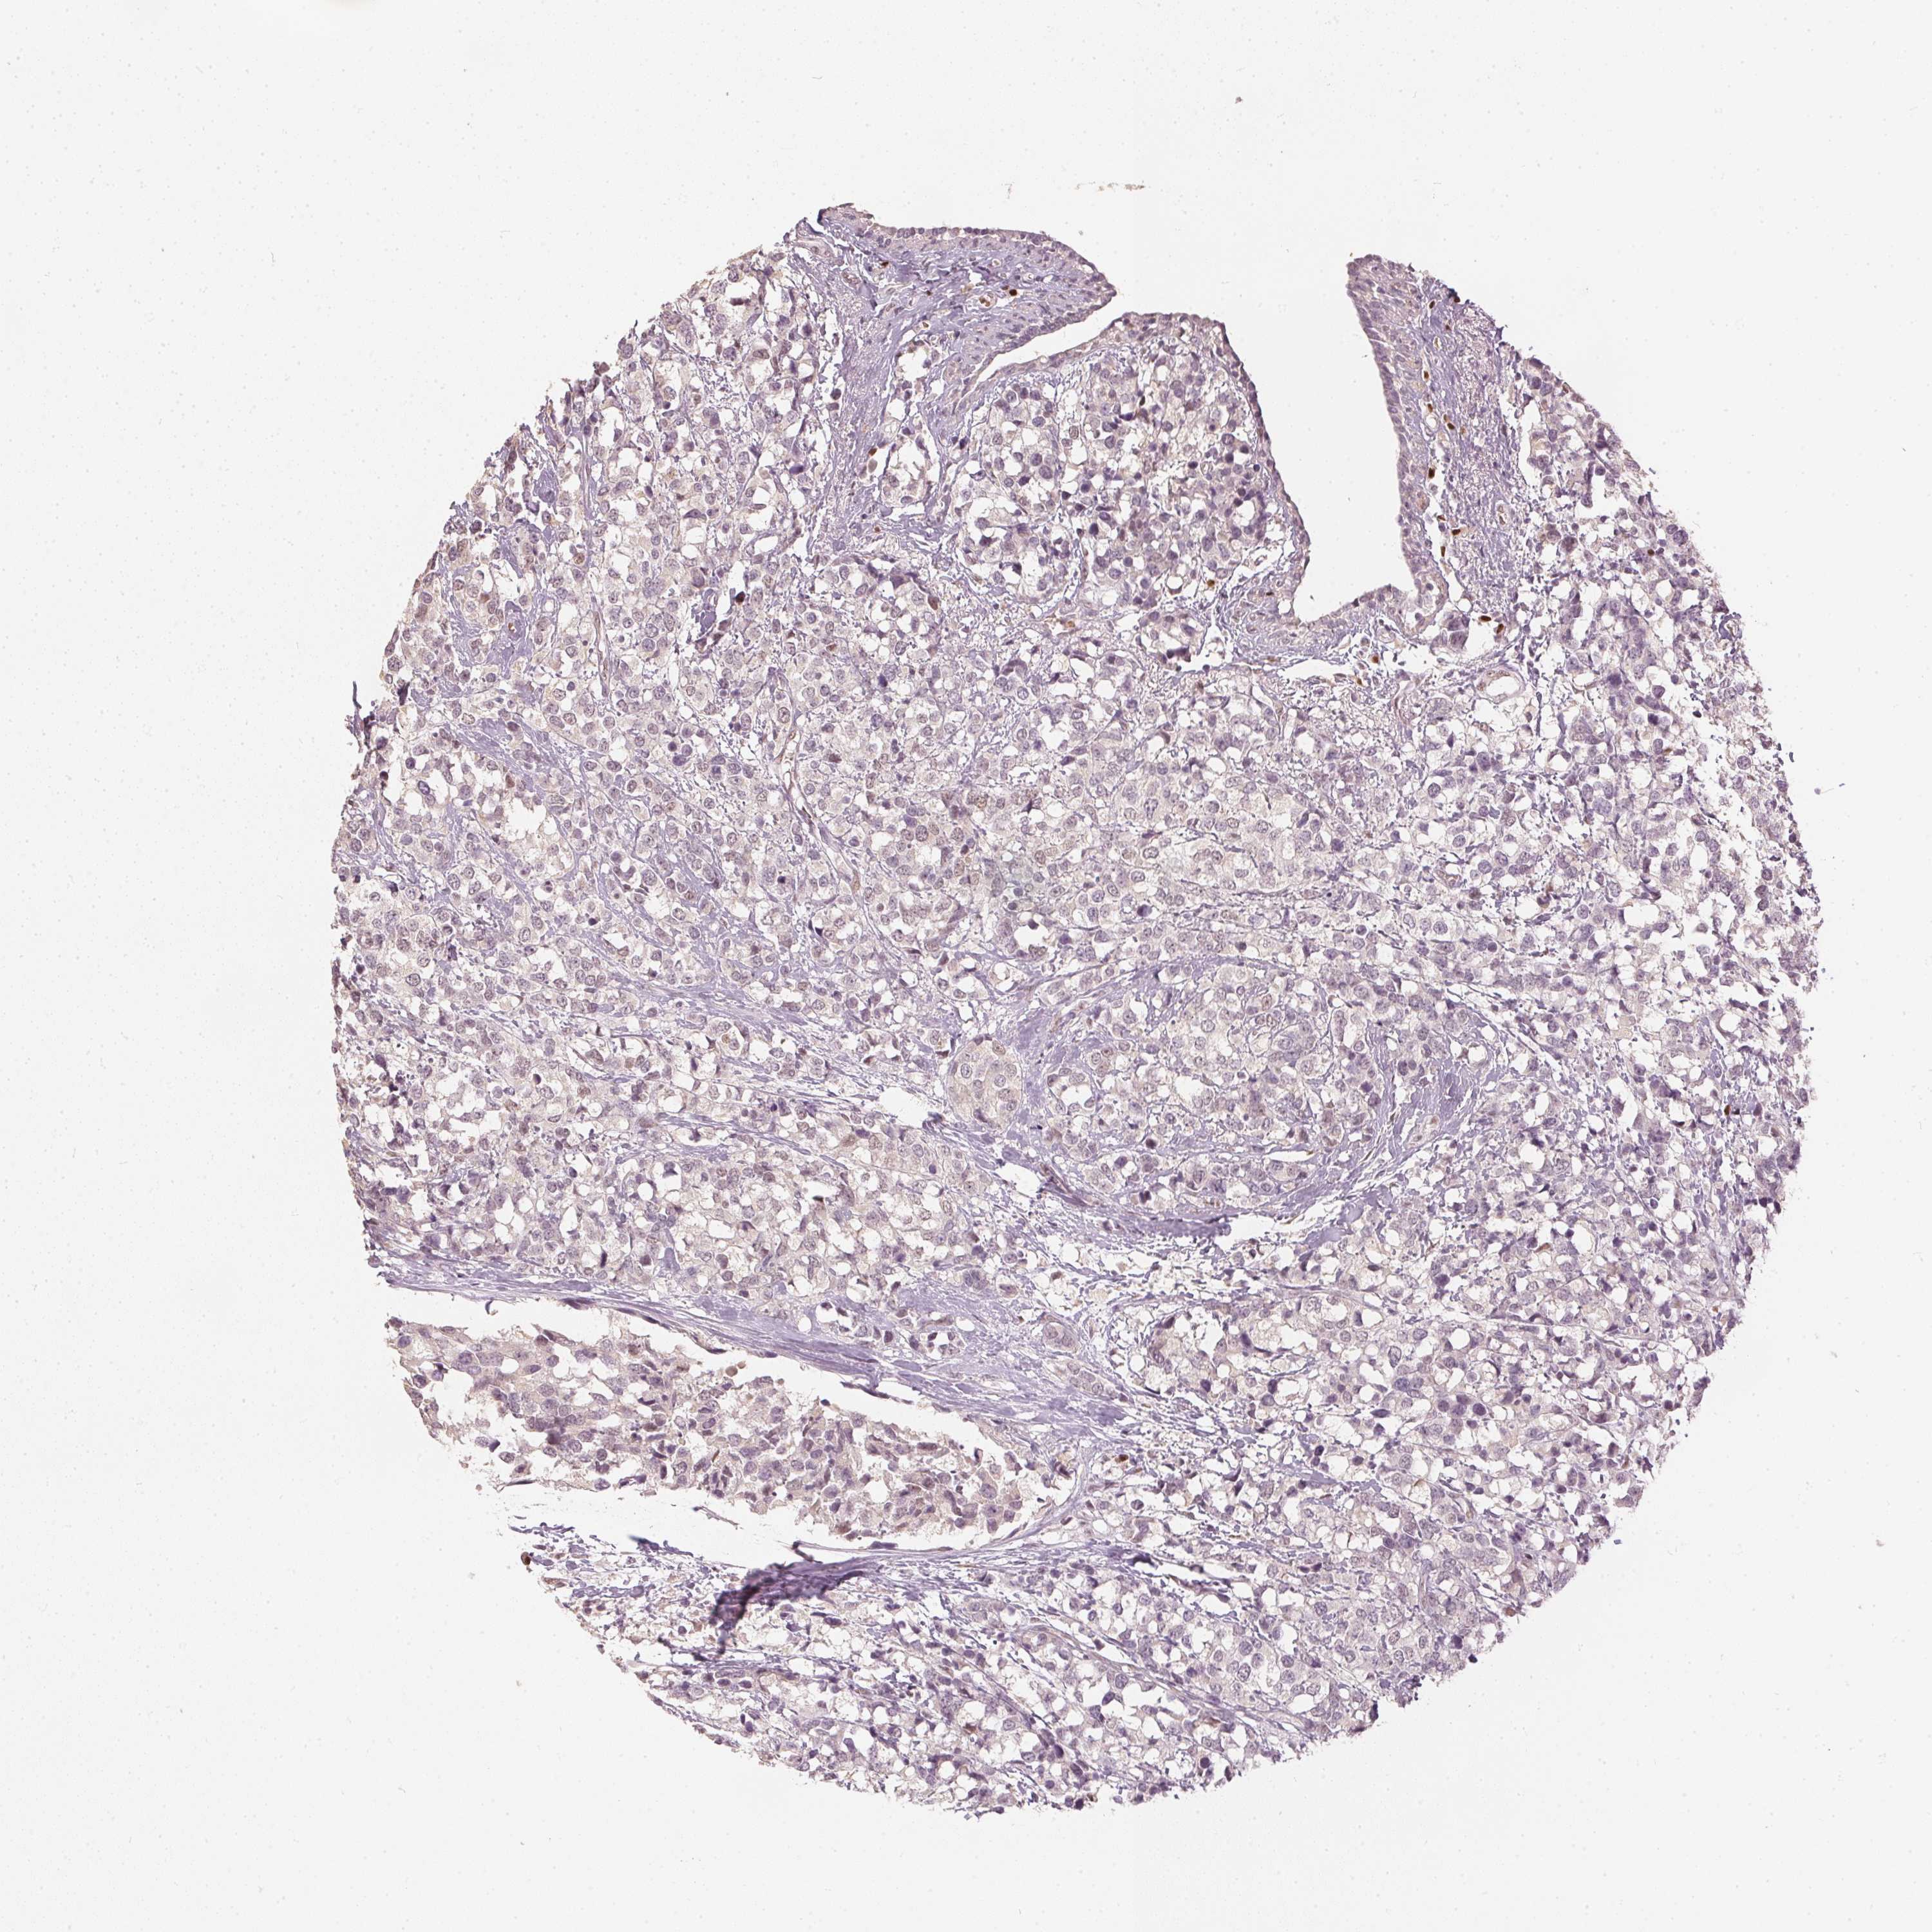

BRCA TCGA BRCA VALIDATION PROTEIN EXPRESSION

ANTIBODIES

AND

VALIDATION